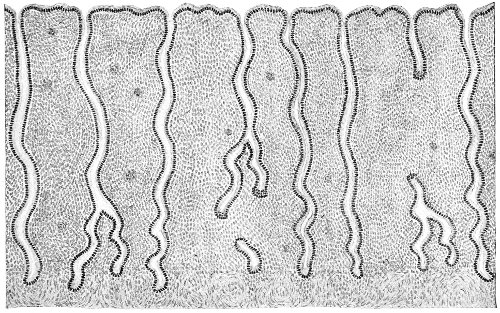

Fig. 22.—Sagittal section showing relations of the several layers of fascia within the pelvic floor (Dickinson).

The vagina extends, as a transverse slit in the pelvic floor, upward and backward, approximately in the direction 60 of a line drawn from the ostium vaginæ to the fifth sacral vertebra. It is approximately parallel with the conjugate of the brim, so that when the woman is erect the long axis of the vagina is inclined at an angle of 60° to the horizon. The vagina is not a vertical open tube: it is a slit in the pelvic floor, in health always closed by the accurate apposition of the anterior and posterior walls (Fig. 21). The anterior vaginal wall is about 2½ inches long in a vertical mesial line. The posterior vaginal wall is about 3½ inches long. The vaginal walls are triangular in shape, being broader above than below. The shape of the normal vagina at the pelvic outlet is shown by Fig. 23. The section here shows the vaginal 61 slit of the shape of the letter H. The portions of the slit extending backward and somewhat outward are called the vaginal sulci or furrows. They are directions of diminished resistance in which tears are liable to occur.

Fig. 23.—Section illustrating the characteristic form of the vaginal cleft (Henle): Ua, urethra; Va, vagina; L, levator ani; R, rectum.] 62